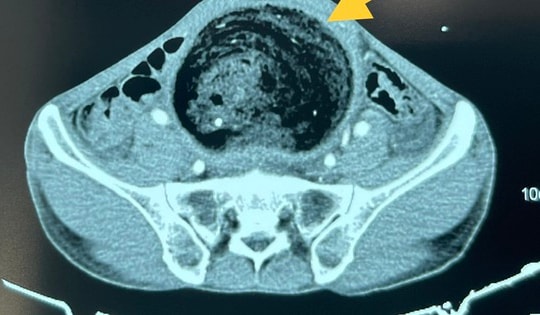

Khi tới Bệnh viện Việt Đức cháu được các bác sĩ thăm khám, chẩn đoán tắc ruột do bã thức ăn. Hình ảnh trên phim chụp cho thấy bã thức ăn di chuyển xuống dưới nhưng bị tắc ở đoạn ruột non cách góc hồi manh tràng 20cm, kích thước 4x2 cm cứng chắc.